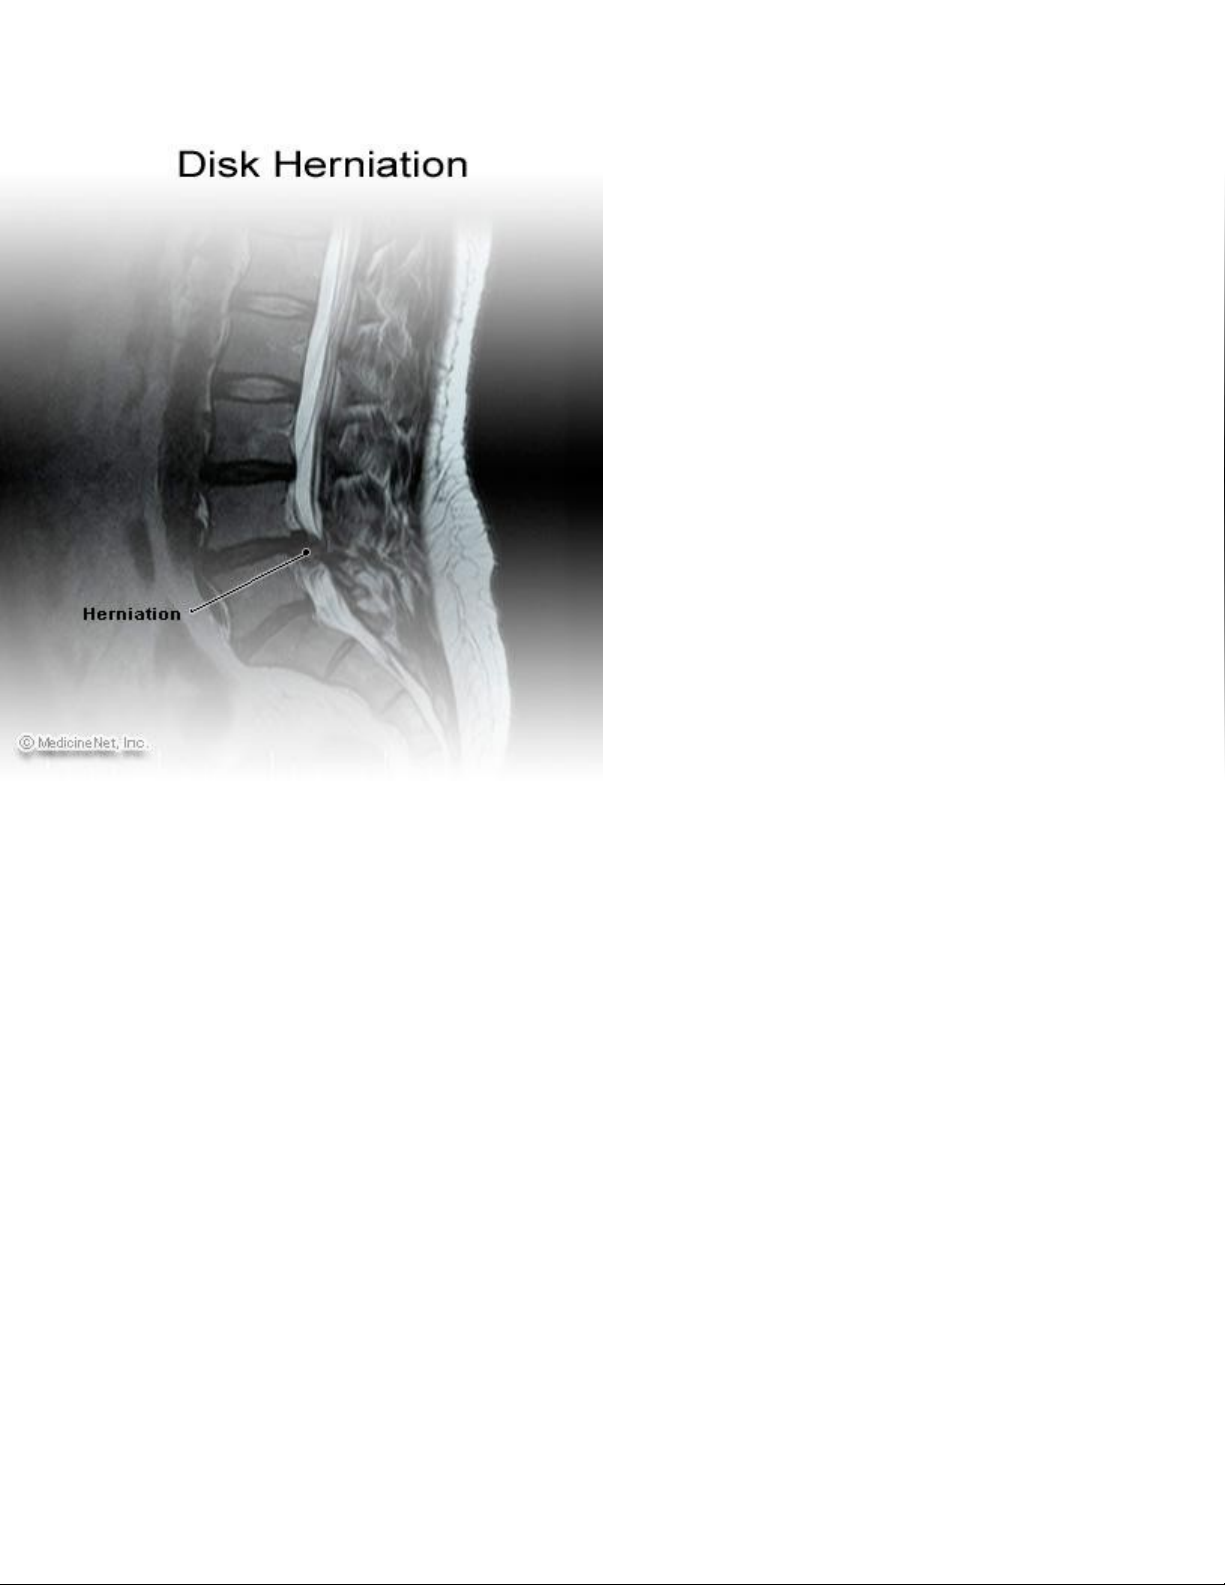

B nh lý r th n kinh là s kích thích th n kinh có nguyên nhân t s h h i c a đĩa đ m gi a cácệ ễ ầ ự ầ ừ ự ư ạ ủ ệ ữ

đ t s ng. T n th ng đĩa đ m này có th do thoái hóa bao x nhân đ m (anulus fibrosus), do ch nố ố ổ ươ ệ ể ơ ệ ấ

th ng ho c c hai. K t qu là ph n m m trung tâm c a đĩa đ m (nucleus pulpose) b thoát v xuyên quaươ ặ ả ế ả ầ ề ủ ệ ị ị

các vòng x c a đĩa và ti p giáp v i t y s ng(spine cord) hay r th n kinh(nerver root) nh là s t n t iơ ủ ế ớ ủ ố ễ ầ ư ự ồ ạ

c a x ng c t s ng. S thoát v này là nguyên nhân ph bi n c a đau th n kinh t a (sciatica) đau tê lanủ ươ ộ ố ự ị ổ ế ủ ầ ọ

xu ng chân. ố

Thoát v đĩa đ m vùng th t l ngị ệ ắ ư